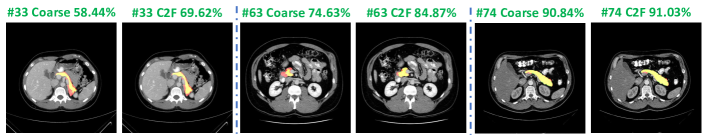

Refer to caption

Figure 4: Examples of segmentation results reported by “ResDSN Coarse” and “ResDSN C2F” on a same slice in the axial view from NIH case #33#33\#33, #63#63\#63 and #74#74\#74, respectively. Numbers after “Coarse” or “C2F” mean testing DSC. Red, green and yellow indicate the ground truth, prediction and overlapped regions, respectively. Best viewed in color.

As shown in Fig 4, we report the segmentation results by “ResDSN Coarse” and “ResDSN C2F” on the same slice for comparison. Note that yellow regions are the correctly predicted pancreas. For the NIH case #33#33\#33, which is the min DSC case reported by both “ResDSN Coarse” and “ResDSN C2F”, the “ResDSN C2F” successfully predict more correct pancreas regions at the bottom, which is obviously missed by “ResDSN Coarse”. If the coarse segmentation is bad, e.g., case #33#33\#33 and #63#63\#63, our 3D coarse-to-fine can significantly improve the segmentation results by as much as 10%percent1010\% in DSC. However, if the coarse segmentation is already very good, e.g., case #74#74\#74, our proposed method cannot improve too much. We conclude that our proposed “ResDSN C2F” shows its advancement over 2D methods by aggregating rich spatial information and is more powerful than other 3D methods on the challenging pancreas segmentation task.